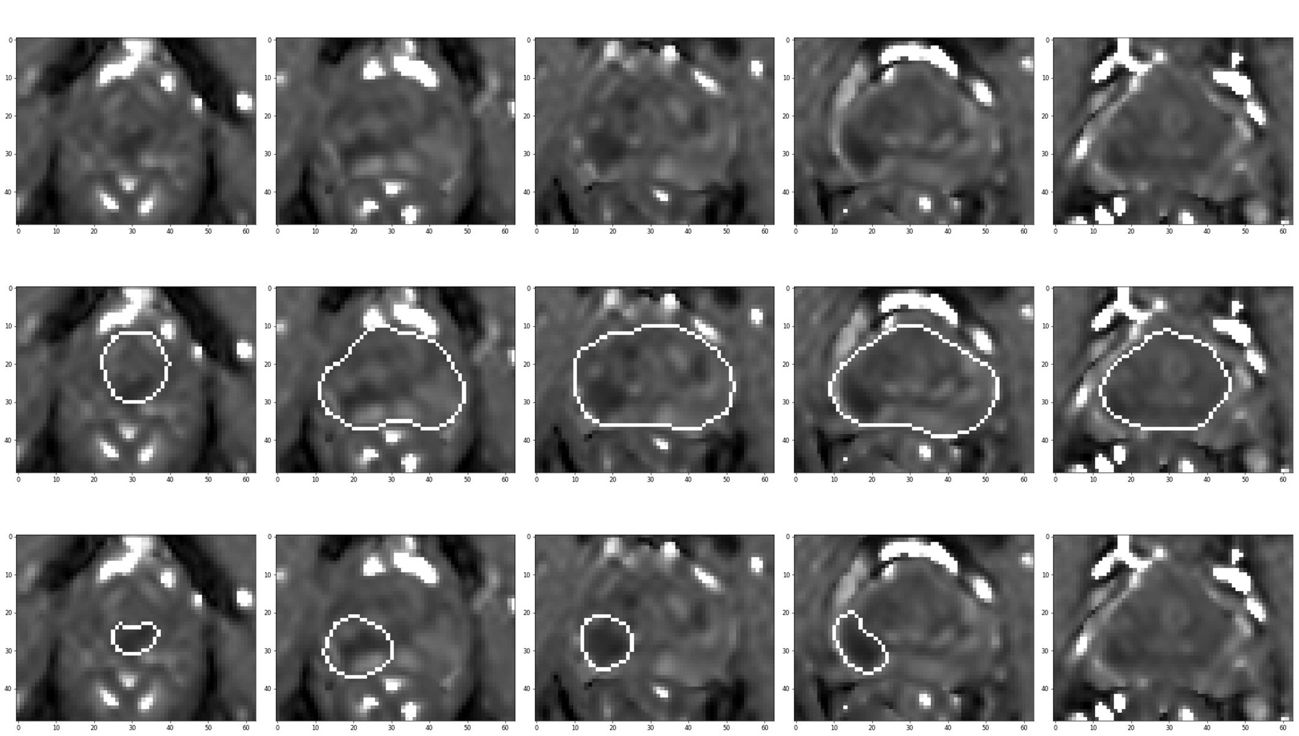

Figure S5: Images from patient no. 1. First Row: ADCm map of prostate. Second Row: prostate delineated. Third Row: tumor delineated

Refer to caption